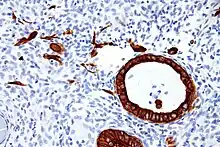

Implantation site intermediate trophoblast. Low molecular weight cytokeratin stain.

- Implantation site intermediate trophoblast[1]

- pleomorphic irregular nuclei, large and hyperchromatic, may show multinucleation

- abundant eosinophilic to amphophilic cytoplasm

- infiltrative growth (splitting muscle, replacing vascular wall ...etc)